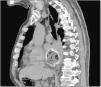

La miopericarditis es una enfermedad poco frecuente, predominando la etiología vírica, pero también puede deberse a una causa traumática directa o indirecta (por contigüidad). Presentamos a un varón de 76 años que acudió por dolor centrotorácico irradiado a escápula de 2 días de evolución, febrícula y disfagia a sólidos y líquidos. Se realizó electrocardiograma (fig. 1) donde se observa una elevación del segmento ST en las derivaciones precordiales. Analíticamente, PCR de 329.6mg/dl y elevación de troponinas de 1,695.8 pg/ml (normal 0-20). Ingresó por sospecha de miopericarditis aguda. Se realizó TC torácica (figs. 2 y 3) que informa de imagen cálcica localizada intraluminalmente en esófago de 55×50mm, que depende de pared esofágica derecha compatible con divertículo epifrénico con material luminal en su interior. Ante los hallazgos, el empeoramiento clínico y la ausencia de respuesta a antiinflamatorios, decidimos la realización de esofagogastroscopia (fig. 4 A y B), en la que se identifica dicho divertículo esofágico, con un hueso de ciruela, una pastilla y restos alimentarios en su interior, que se extraen secuencialmente con asa. Cabe destacar la presencia de lesiones por decúbito en la mucosa intradiverticular (fig. 5). Probablemente, la miopericarditis fuera producida por causa mecánica debido a la afectación del miopericardio por la inflamación transmural provocada por los cuerpos extraños retenidos en el divertículo (figs. 2 y 3). Tras la extracción, el paciente mejora y es dado de alta en 72 h.